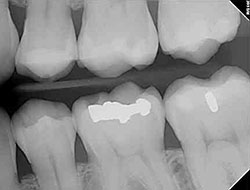

Digital X-Rays

Using the most advanced dental technology possible is just as important as staying up-to-date on the latest treatment techniques. Because our practice is dedicated to providing you with the safest and most convenient treatment options available, we utilize advanced digital X-ray technology in our office.

Digital X-rays provide several advanced imaging options that are designed to save time, provide clearer dental photos, and expose patients to less radiation than with traditional X-ray technology.

Our practice is focused on making your dental experience as comfortable as possible. At your next appointment, we’ll be happy to answer any questions you may have.